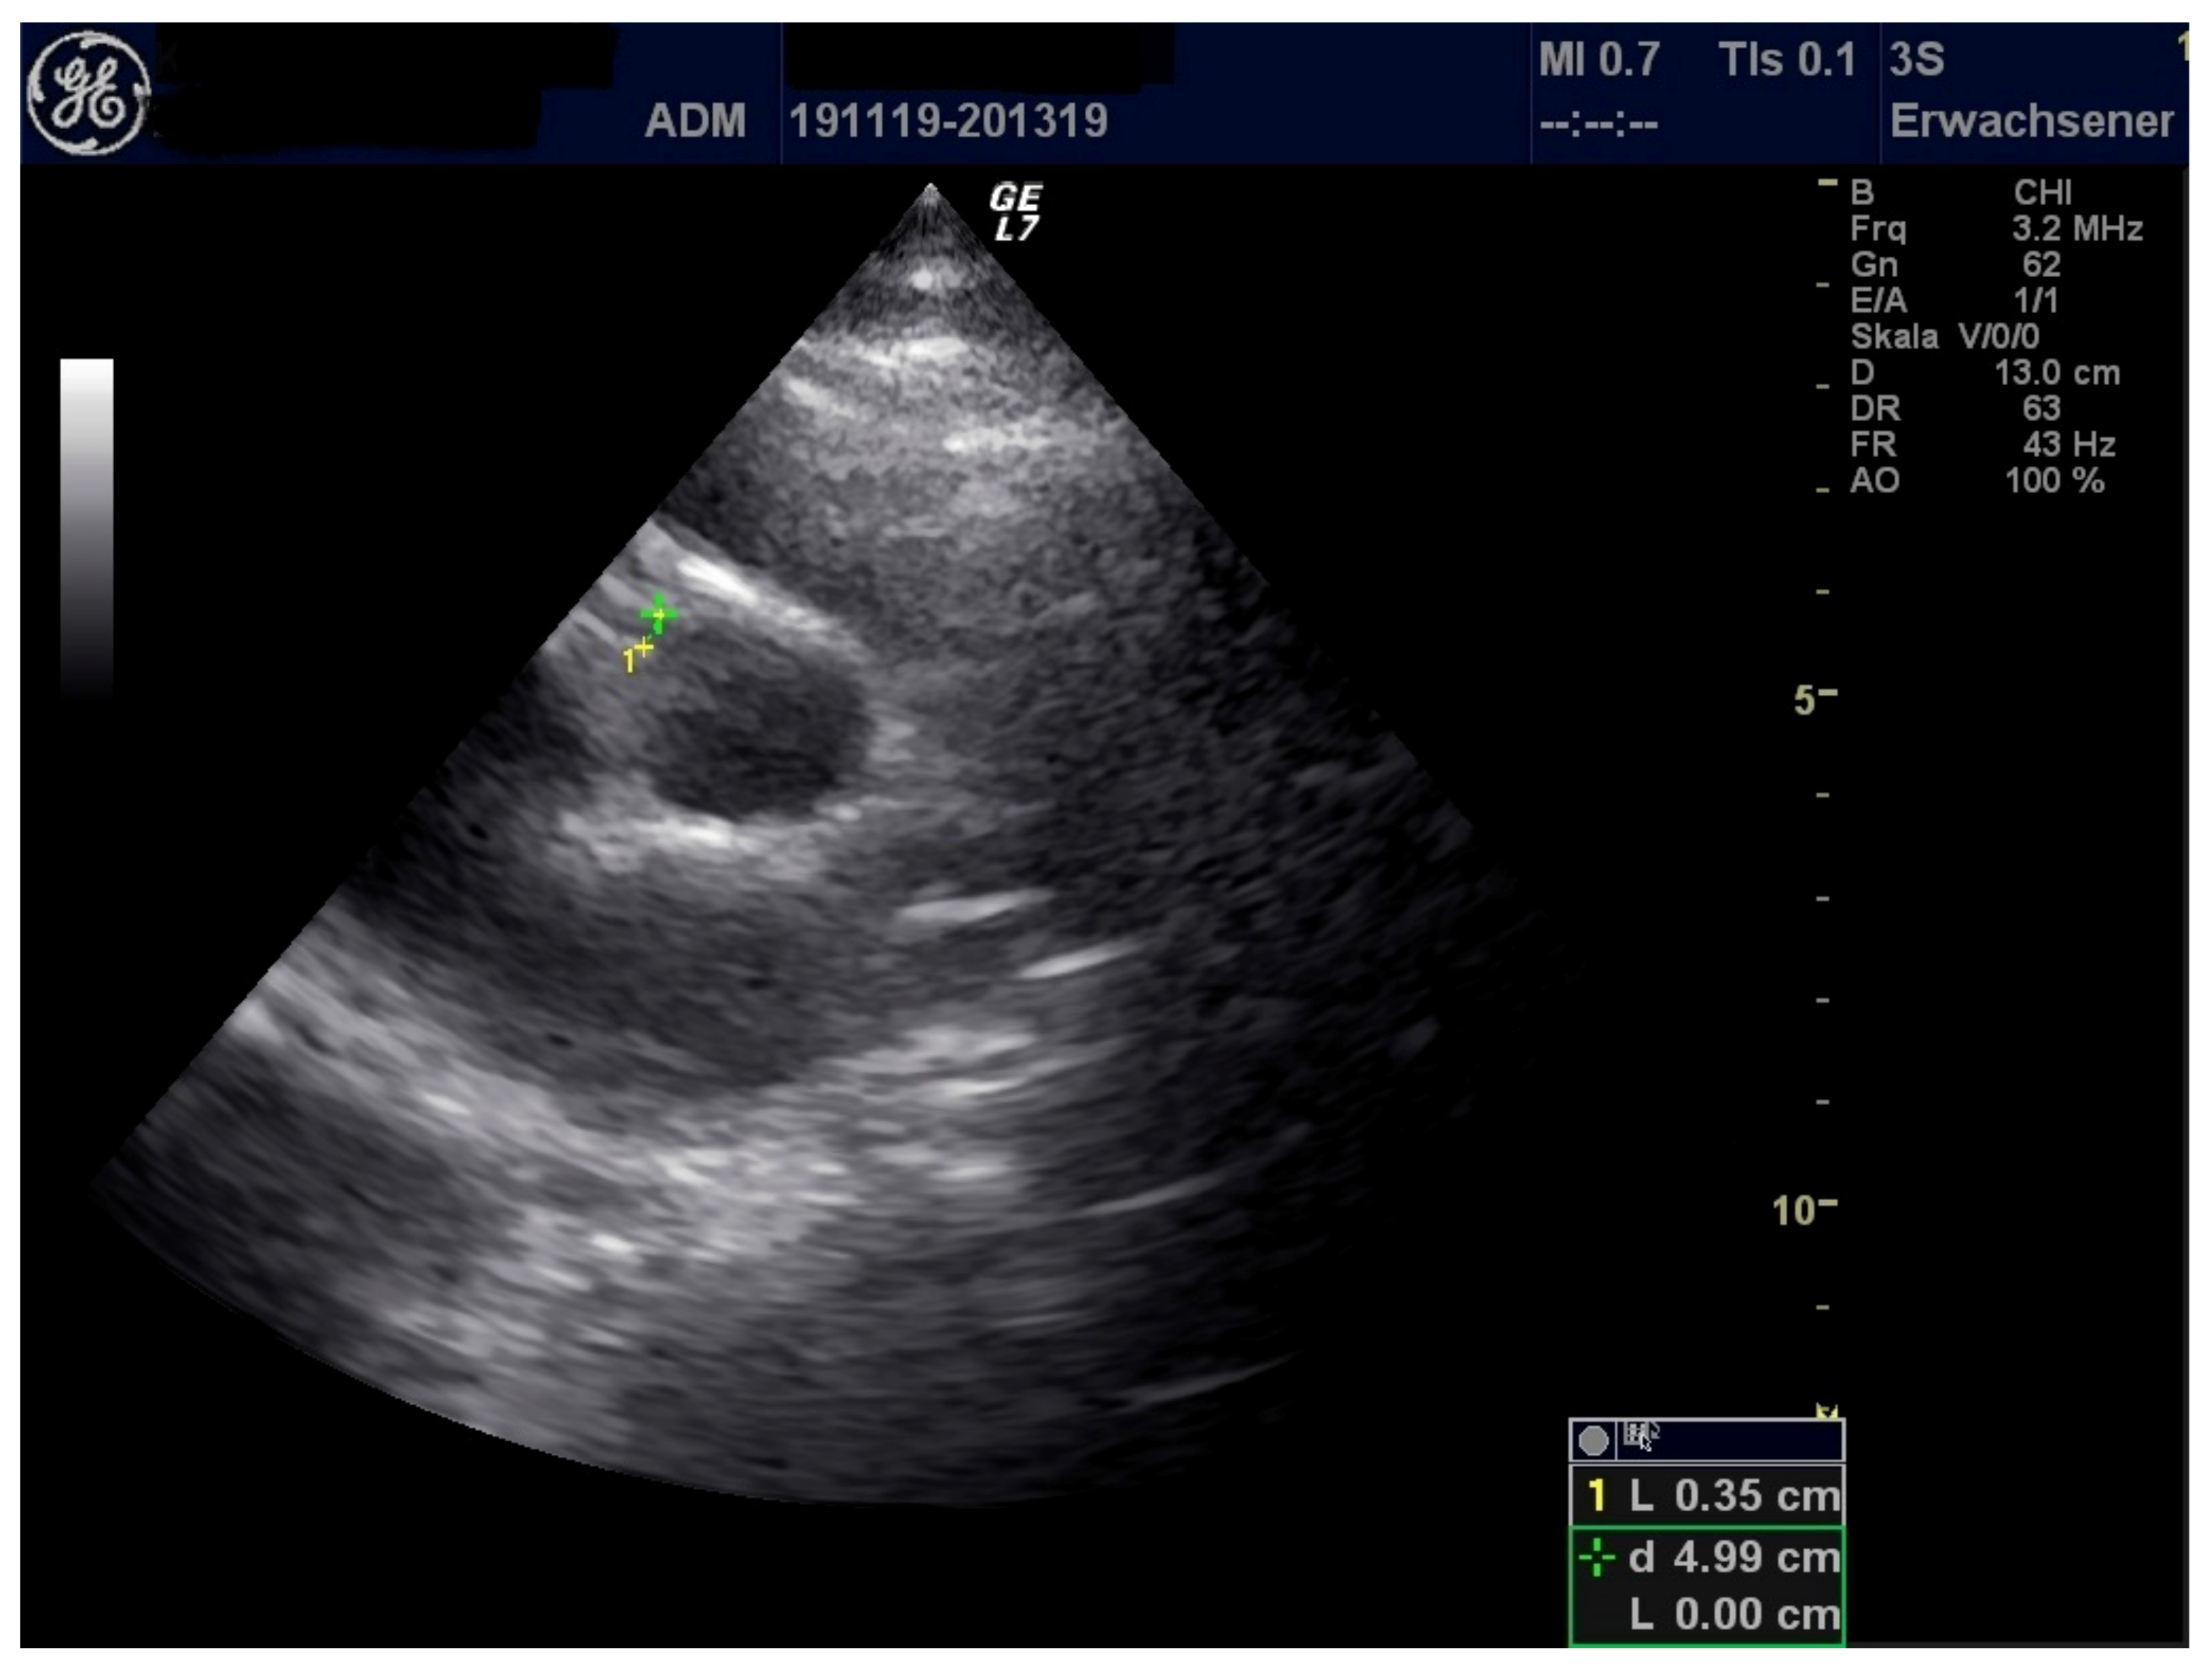

| LCA (mm) | 3.8 | 3.3 | 3.1 |

| RCA (mm) | 3.2 | 4.0 | 2.8 |

| Pericardial effusion (mm) | 7 | 3 | 5 |

| Pleural effusion (mm) | 9 (left), right 0 | 0 | 0 |